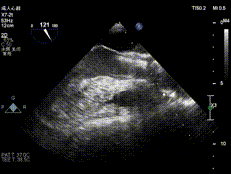

超声评估:

术前超声:L-R窦之间融合,大量反流

术后超声:瓣膜植入位置良好、形态完整,反流消失